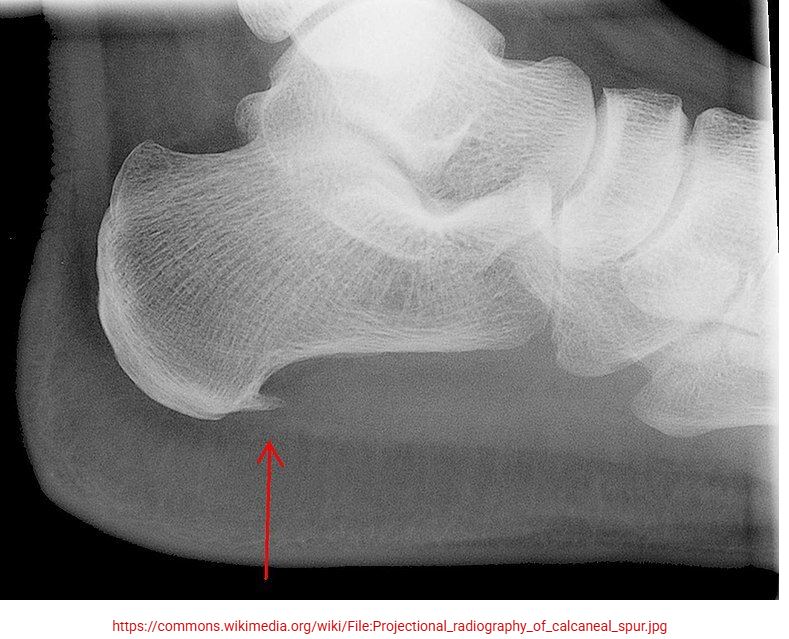

اگرچه پیشرفت تکنولوژیکی تکنیکهای تصویربرداری مانند MRI و اشعه ایکس به طور قابل توجهی حوزه مراقبتهای بهداشتی را بهبود بخشیده است، اما در برخی موارد منجر به استفاده غیرضروری از آنها نیز شده است. شنیدن اینکه علت ساده درد پاشنه پا، خار استخوانی است، برای افراد غیرمعمول نیست. با این حال، نشان داده شده است که خار پاشنه ممکن است هیچ تاثیری در ایجاد یا پیشآگهی فاشیلیت پلانتار نداشته باشد [13]. آنها به شدت با چاقی مرتبط هستند و به نظر میرسد با افزایش سن بسیار رایج هستند، زیرا در 55٪ از افراد بین 62 تا 94 سال یافت میشوند [28]. بنابراین، توصیه کلی این است که تصویربرداری را برای افرادی که هیچ نشانهای از بهبود با مدیریت محافظهکارانه نشان نمیدهند، رزرو کنید [23].